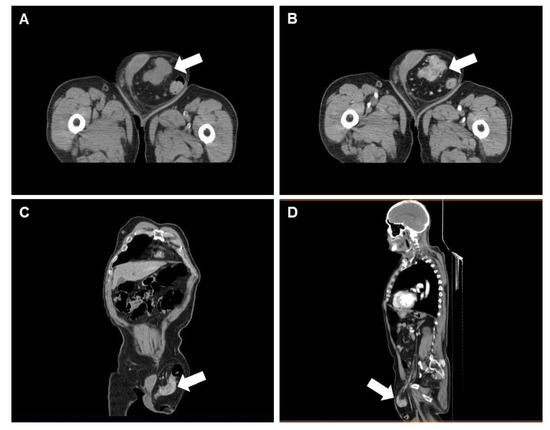

A Rare Case of Sigmoid Colon Carcinoma in Incarcerated Inguinal Hernia

2. Case Report